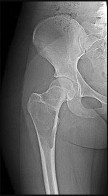

Figures 13a and 13b are the radiographs of a 57-year-old man who is seen in the emergency department. He has been experiencing left thigh pain for 2 month. Four years ago he underwent laparoscopic nephrectomy and states that he has been disease free since the resection (although he has not seen a doctor in 2 years). The pathogenesis of osteolysis in renal cell carcinoma metastatic to bone includes secretion of parathyroid hormone-related peptide (PTHrP), transforming growth factor-B (TGF-B), and vascular endothelial growth factor (VEGF), which directly cause overexpression receptor activation of nuclear factor kB ligand (RANKL) on which cells?

Tumor cells in renal cell carcinoma interact with the bone microenvironment to drive bone destruction and tumor growth by secreting factors such as PTHrP, TGF-B, and VEGF. These factors stimulate the host osteoblast, causing overexpression of RANKL, which in turn causes bone resorption through stimulation of osteoclasts. RANKL expression is upregulated in many types of metastatic cancer to bone, and blocking the RANK/RANKL interaction prevents progression of metastases.

Other actions of RANKL include triggering the migration of human tumor cells that express RANK. RANK and RANKL are expressed in metastatic renal cell carcinoma, and their presence strongly signifies potential recurrence. The use of denosumab, which binds and inactivates RANKL, has its basis in these findings in renal cell carcinoma.